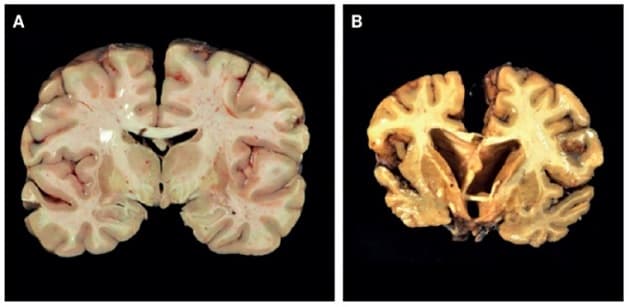

Kronisk traumatisk encefalopati (KTE) dækker over en demenslignende tilstand, som formodes at være forårsaget af multiple mindre alvorlige slag mod hovedet. KTE blev beskrevet allerede for 100 år siden hos boksere og er i de seneste år kommet i søgelyset bl.a. hos pensionerede professionelle, amerikanske fodboldspillere. Statusartiklen af Pourhadi et al opsummerer vores viden om prævalens, klinisk præsentation, diagnostik og patofysiologiske mekanismer. Forfatterne konkluderer, at tolkningen af kliniske symptomer og sammenhæng med patologien ofte vanskeliggøres af komorbiditet og psykosociale faktorer, som ofte resulterer i betydelig diagnostisk forsinkelse.

Kronisk traumatisk encefalopati